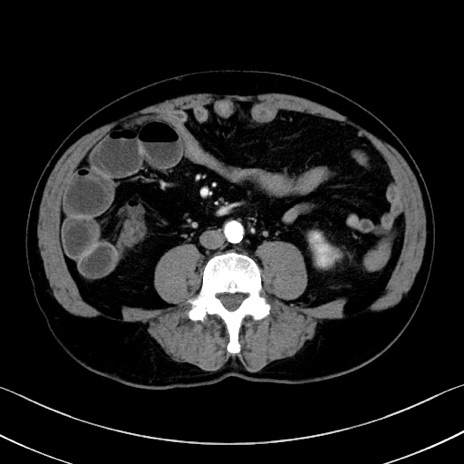

症例35(横断像)

【症例】70歳代 男性

【主訴】腹部膨満、嘔吐

【現病歴】昨日より腹部膨満感出現。本日増悪し、仙痛出現。嘔吐あり、受診。

【既往歴】糖尿病、胆摘後

【身体所見】BP 149/80mmHg、HR 74/min、BT 35.9℃、腹部:膨満、軟、圧痛なし。腸雑音減弱あり。上腹部正中切開瘢痕あり。

【データ】WBC 13500、CRP 1.72